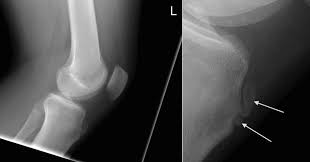

Knee disease osgood schlatters in adults. In four cases a true joint had formed between an ossicle in the patellar ligament and a facet on the tibia. Osgood-Schlatter disease is a painful condition causing inflammation just below the knee. The tendon below your kneecap called the patellar tendon attaches to the tibial tuberosity on the shinbone called the tibia.

Osgood Schlatter disease or Osgood Schlatter lesion is a very common cause of knee pain in children between the ages of 10 and 15 years old. An adhesive tape is placed across the part of the bone that is tender and swollen the tibial tuberosity while the patients knee is bent. Osgood-Schlatter is a common disease with most cases resolving spontaneously with skeletal maturity.

Friday April 05 2019. Pain that gets worse with exercise or activity. Seven adults with the sequelae of Osgood-Schlatters disease presented after experiencing symptoms for an average of eight years. Osgood Schlatter disease symptoms. Osgood-Schlatter exercises are used to strengthen the muscles around the knee joint principally the quadriceps hamstrings and gastrocnemius muscles. Common in adolescents during growth spurts Osgood-Schlatter disease can affect adults if not properly assessed and treated. Pain and tenderness in front of the knee. This bony protrusion is called the tibial tuberosity. Adults with continued symptoms may need surgical treatment if they fail to respond to conservative measures.

Osgood-Schlatter is a common condition in young athletes and growing adolescents that refers to inflammation of a growth plate at the knee. Osgood Schlatter Disease Surgery In extreme cases surgery may be used to get rid of Osgood-Schlatter disease. Osgood-Schlatter is a common disease with most cases resolving spontaneously with skeletal maturity. The purpose of this study is to describe. The pain may come and go. There may also be inflammation of the patellar tendon which stretches over the kneecap. Osgood-Schlatter is a common condition in young athletes and growing adolescents that refers to inflammation of a growth plate at the knee.